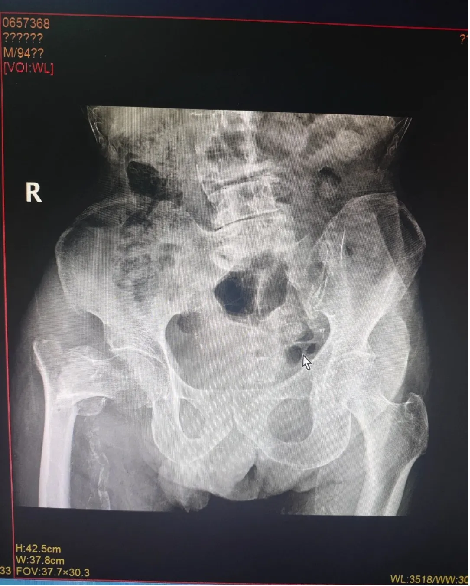

近日,醫(yī)院成功為97歲高齡患者實施右股(gǔ)骨粗隆間骨折閉合複位(wèi)髓內釘內固定術(PFNA)。

患者餘(yú)某,男性,97歲高齡,因在家不慎摔傷致右股骨粗隆間骨折住院治療,入院診斷:右股骨粗隆間骨折,中度貧(pín)血,嚴重營養不良,嚴重骨質疏鬆,低鉀血症,腦梗死(sǐ)後遺症,高血壓病(bìng),慢支肺氣腫。創傷骨科在接診後,迅速為患者開通“高(gāo)齡骨折綠色生(shēng)命通道”,組織心血(xuè)管(guǎn)內科、呼吸內(nèi)科、營養科、麻醉科等多學科會診(zhěn)後,全麵評估病情、嚴格把控圍手術期各(gè)項指標,精心(xīn)定製手(shǒu)術方案與術後風險預案,經與患者及家屬溝通同意手術後,在椎管內麻醉下行(háng)“右股骨粗隆間骨折閉合複(fù)位髓內釘(dìng)內固定術”,經多學科(kē)協作在患者入(rù)院48小時內最佳手術窗口(kǒu)期完成(chéng)手術,術後指導功能鍛煉(liàn),最大可能避免了老(lǎo)年髖部骨折如血栓,壓(yā)瘡,墜積性肺炎等致命性並(bìng)發症,患者入院治(zhì)療10天後康複出院。患者及家屬對醫院的醫療水平給予了高度的肯定,對醫護人員的辛勤付出表達了衷(zhōng)心的感謝!